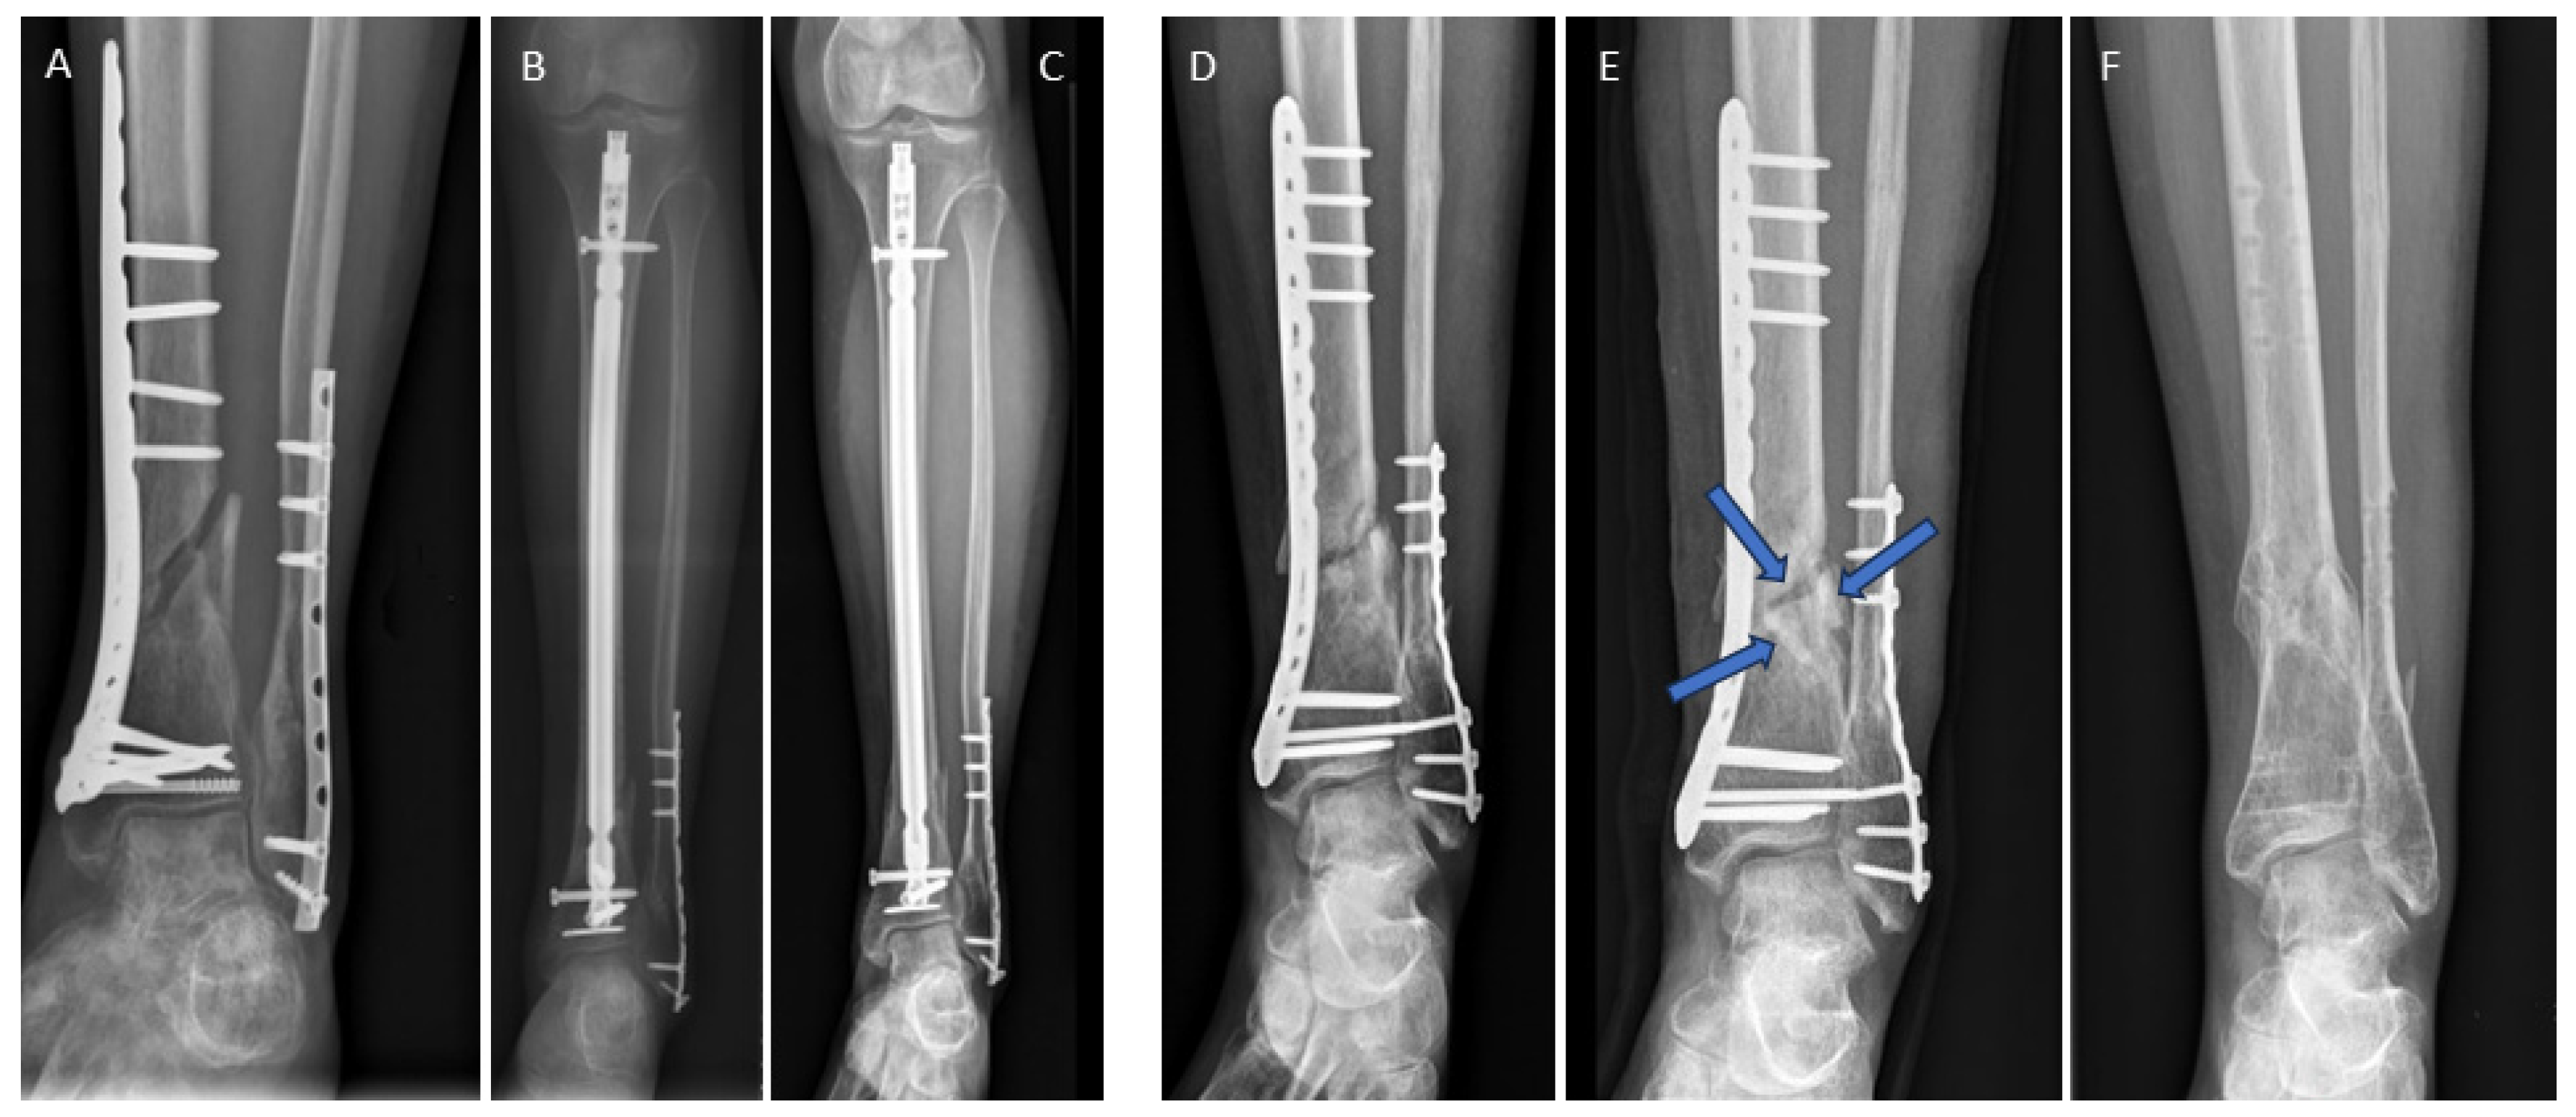

3.4. Examples for Bone Healing

3.5. Clinical Complications

3.6. Radiological Findings of Interest